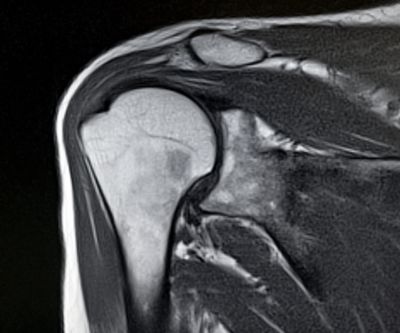

The gold standard for diagnosing rotator cuff tears is MRI. This type of scan utilizes a powerful magnet to create images of the anatomy deep inside the shoulder. An ultrasound is another study that can reliably diagnose rotator cuff tears, though it is operator dependent and provides less information about the quality of tissue, tendon retraction, and muscle atrophy. An X-Ray is another important study to assess for trauma and degeneration within the shoulder.